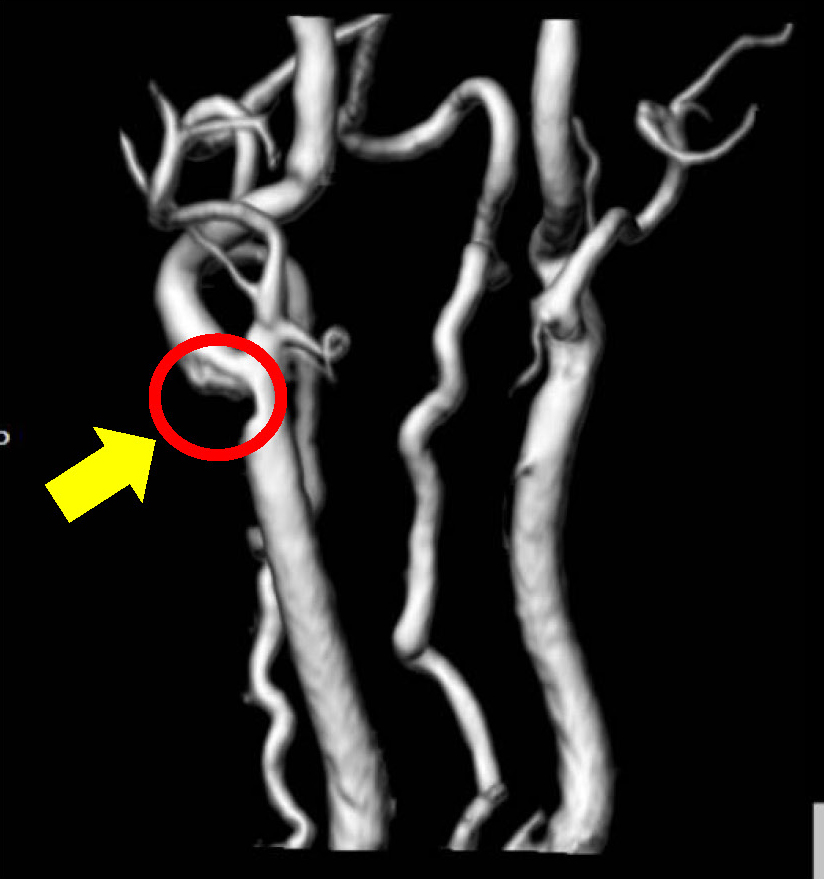

頭部MRA検査での1例

頭部MRA検査とは、造影剤を用いることなく、脳の血管を立体的に撮影をすることができる検査です。

脳の血管の狭窄や閉塞及び、脳動脈瘤を発見することが可能です。

未破裂脳動脈瘤

未破裂脳動脈瘤とは、脳動脈の壁に瘤のような部分があり、出血などの徴候がない状態のことです。症状がないことが多いのですが、破裂すると「くも膜下出血」を引き起こす可能性もあります。多くの脳動脈瘤の破裂率は高くないため、基本的には、治療を急ぐ必要はございませんが、高血圧の方や喫煙される方は他の方と比べて、破裂しやすいので、注意が必要です。